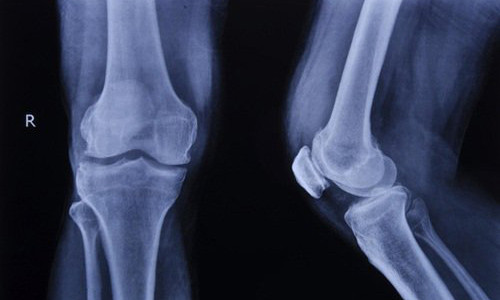

| Ảnh minh họa. |

Ngoài ra, để biết chắc xương có gãy hay bị rạn hay không, bạn phải đến bệnh viện để chụp X-quang.